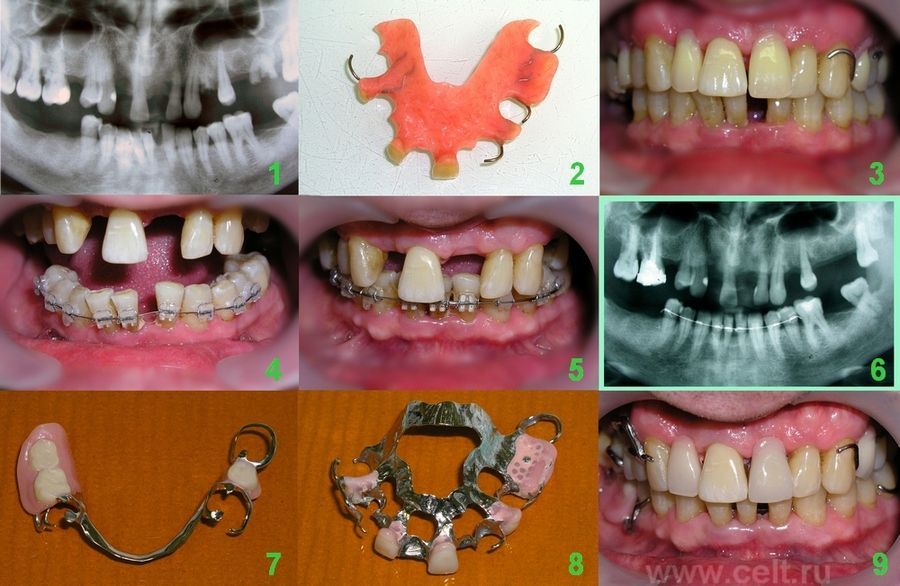

На представленных фотографиях проследим этапы проведения стоматологического лечения:

1) На панорамном рентген.снимке корни и остатки зубов перед удалением.

2) Изготовлен временный пластинчатый протез на верхний зубной ряд

3) Пластинчаый протез

4) На нижний зубной ряд наклеены брекеты и установлена дуга

5) Выравненный зубной ряд

6) Контрольный снимок, установлен ретейнер с язычной стороны

7) Бельный протез на кламерах на нижний зубной ряд

8) Бельный протез на кламерах на верхний зубной ряд

9) Снимок по окончании лечения. Достигнутый результат